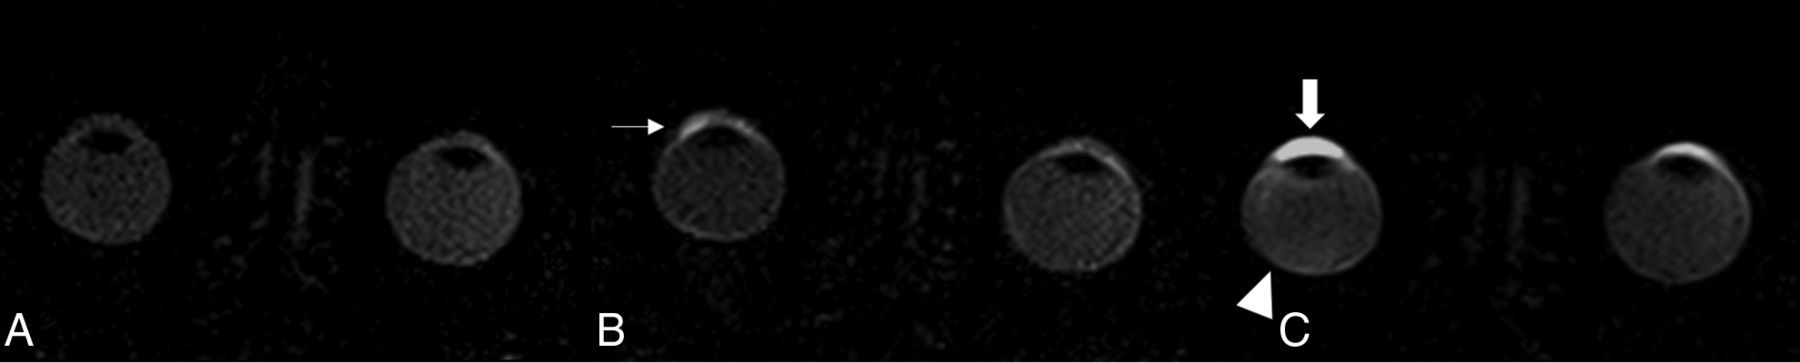

Patients with disorders in the PEC had higher levels of contrast enhancement in the central AC (mean relative SI120min = 2.49, SD120min = 1.80, p120min = .041) compared with the control group (mean relative SI120min = 1.79, SD120min = 1.39) and in the VB (mean relative SI120min = 0.44, SD120min = 0.64, p120min = .006) after 120 minutes compared with the control group (mean relative SI120min = 0.16, SD120min = 0.43). Other regions, including the lateral AC, showed no differences compared with the control group (Table 2 and Figs 4 and 5).

Example of a patient with a disorder in the PEC (retinal). Native scan (A), 20 minutes after gadolinium injection demonstrating a pathologic permeability of Gd at the blood-retinal barrier (small arrows) (B), and accumulation of Gd in the VB after 120 minutes (arrowhead) demonstrating an opposite pathway of Gd (C). The physiologic enhancement in the anterior eye segment can also be seen in C, independent of the pathology of the posterior eye segment.